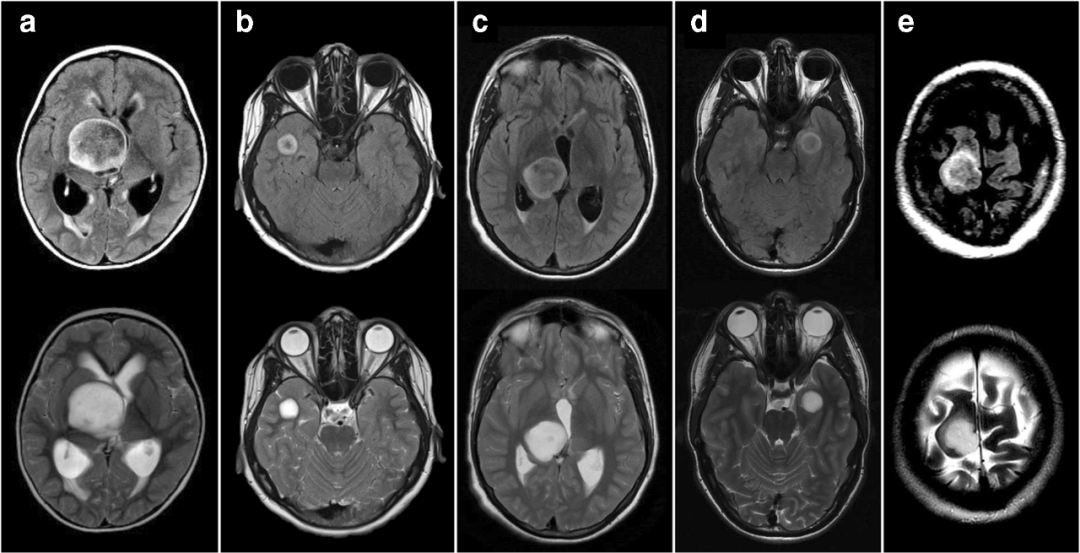

4 例 T2-FLAIR 错配,但是年龄 ≤18 岁,a = 2 岁(毛细胞星形细胞瘤),b = 12 岁(病理提示灰质异位,随访 1.5 年时无进展/复发的证据),c = 14 岁(H3K27M 改变型中线胶质瘤),d = 18 岁(儿童低级别弥漫星形细胞瘤,MYB 改变)。